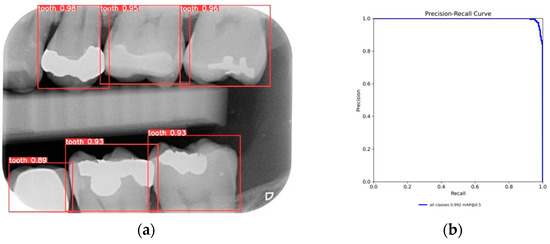

After training the YOLO object-detection models, this study tested unlabeled, and untrained the BW images. The test results are illustrated in Figure 10. The four object models used in this study, along with the image-augmentation technique, successfully identified all the teeth of interest in the BW images. After the image-segmentation stage, the extracted regions were delineated by the red boxes in Figure 10a, and the PR curve is shown in Figure 10b. The results extracted are depicted in Figure 11, effectively capturing the individual teeth and their edges and enabling further image-enhancement and CNN training steps.

Figure 10.

YOLO validation results: (a) YOLOv8 detect results; (b) YOLOv8 validation PR curve.